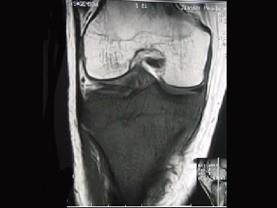

问题 患者女,28岁,右膝跌伤伴疼痛9年,加重及活动障碍1年半,经药物治疗及理疗后病情无好转,既往无特殊病史,查体跛行步态,触痛,请结合所提供的图像,选择最佳选项 ( )

选项 A、软骨肉瘤 B、骨巨细胞瘤 C、滑膜肉瘤 D、骨肉瘤 E、结核

答案 C